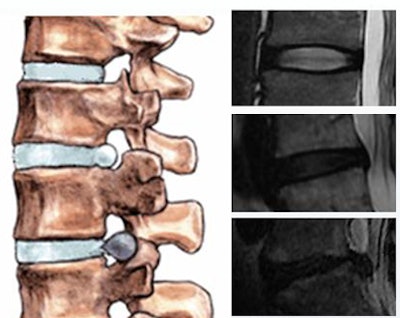

| Intervertebral disk herniation is seen in the localized displacement of disk material beyond the limits of the intervertebral disk space -- either protrusion or extrusion. All images courtesy of Sofia Michopoulou. |